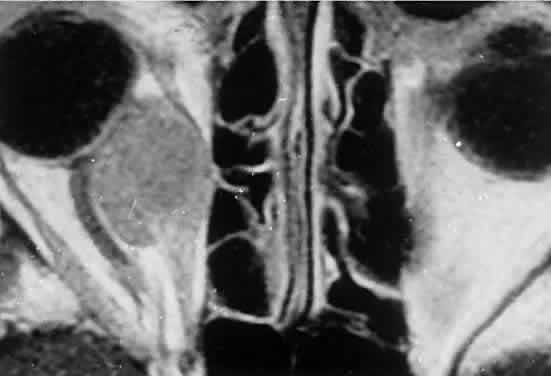

Within the orbit, rhabdomyosarcoma occurs most often, but not exclusively, in the superior nasal quadrant, with downward and outward displacement of the globe. CT scans show the topography of the orbital mass (Fig. 1A), as well as the possible extension into adjacent bone, paranasal sinuses, or the intracranial cavity. The circumscription that may be noted on CT is relative, because the lesion is not encapsulated and microscopically infiltrates normal tissue. Echography shows internal echoes of low-to-medium amplitude. Because the cellular tumor absorbs acoustic energy, the amplitude of the spikes falls off somewhat through the lesion (see Fig. 1B and C). MRI can help define the tumor's relationship to extraocular muscles (Fig. 2).

Fig. 2. MRI shows an intraconal tumor of lower intensity than the medial rectus muscle. The proximal muscle is splayed rather than compressed, suggesting that the lesion originated within the medial rectus. The diagnosis was alveolar rhabdomyosarcoma.